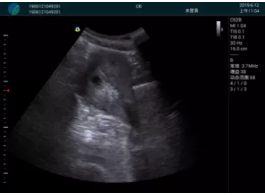

清晰顯示孕囊,通過軟件包計算孕齡7w+6d

M20實時引導(dǎo),術(shù)中清晰顯示孕囊被破壞和抽吸針的過程,清晰顯示吸引針

抽吸結(jié)束后縱切子宮,孕囊已被完全抽吸,未見明顯殘留

橫切子宮,發(fā)現(xiàn)右側(cè)宮腔靠近宮角處有少許脫模樣殘留

M20引導(dǎo)下,抽吸針找到右側(cè)宮角處再次清掃

二次抽吸后再次進行超聲檢查,宮腔未見殘留,宮腔線清晰顯示